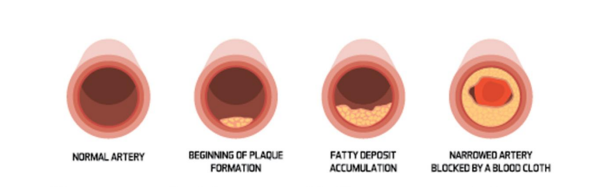

심장에서 머리로 올라가는 동맥을 초음파로 보는 검사입니다① 혈관벽(Intima-mediathickness(IMT) 두께가 0.9mm이상으로 두꺼우거나 정상치의 75th percentile 이상이면 이상으로 간주합니다.② 혈관의 혈전(plaque)이 최근 혈관벽의 두께보다 더 중요한 의미를 가지는데 주변벽보다 50% 이상 두껍거나 1.5mm 이상 혈관벽의 두께를 나타내면 plaque가 있는 것으로 보입니다. 두께도 중요하지만 떨어져 가면 뇌졸중이기 때문에 혈전이 어떤 형태인지도 중요합니다.③ 혈관이 70% 이상 좁아진 경우에는 혈관 시술을 고려해야 합니다. stent를 넣거나…